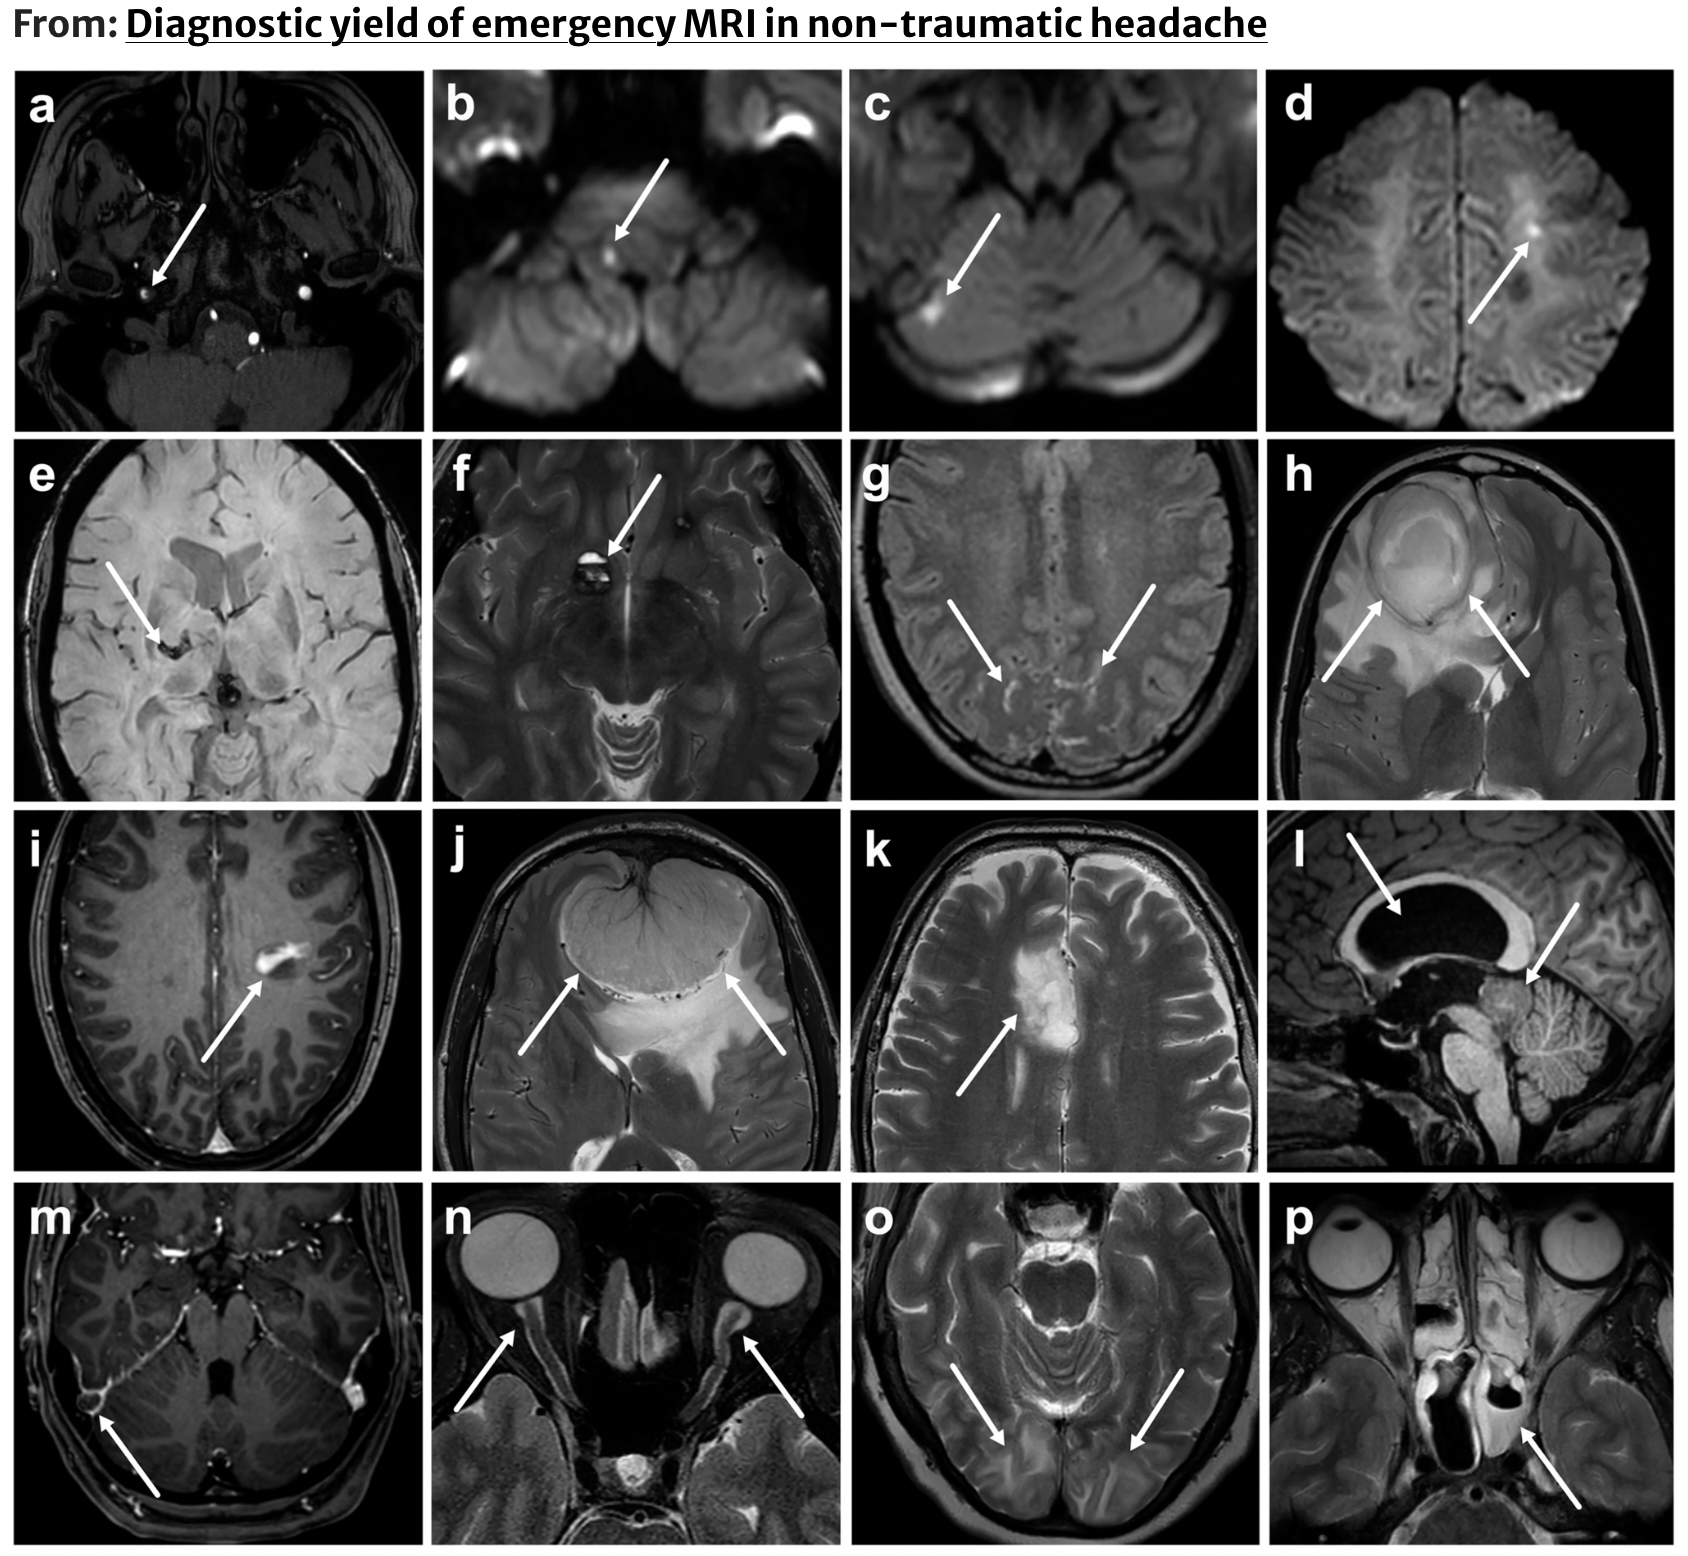

Emergency Radiology

My research examines the diagnostic accuracy, imaging yield, and clinical value of radiological imaging in emergency settings